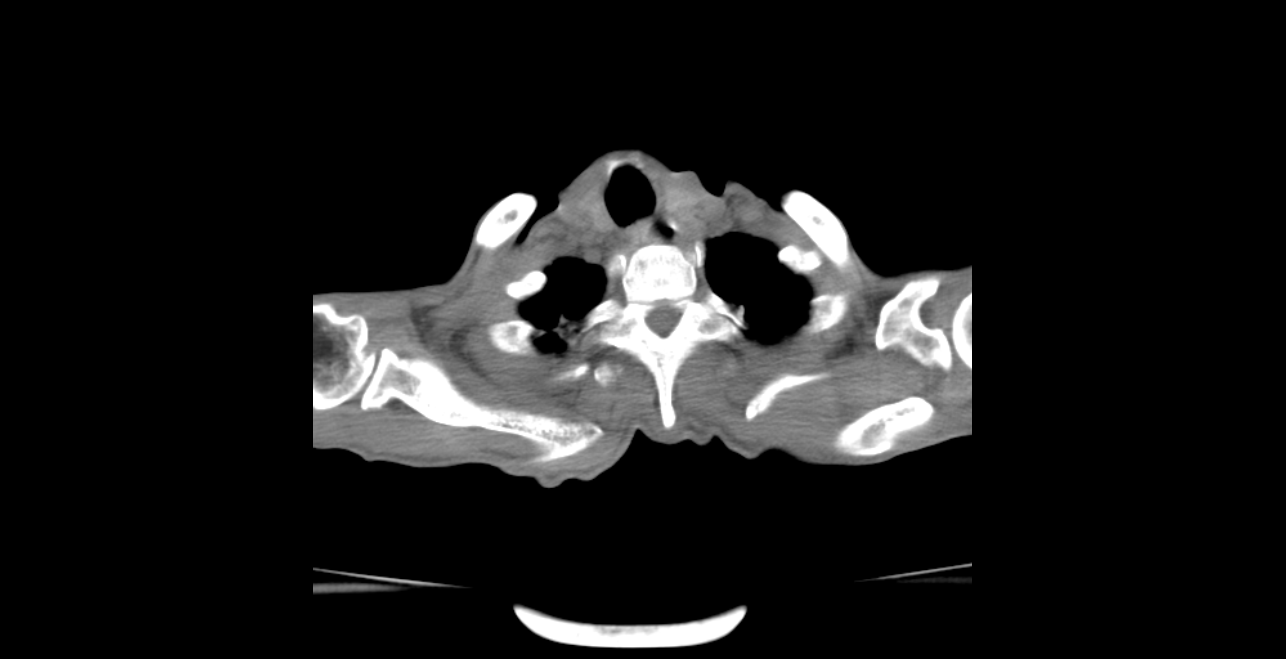

CT52960:患者一年内极度消瘦

患者一年内极度消瘦,请大家看看右主支气管内是占位?

右肺及左上下肺均可见斑片纤维索条网线状影,右肺尤著。右侧胸腔背侧及侧胸壁及少许液体密度影。两肺透光度减低及多发小圆形低密度影。考虑:慢支炎、小叶中心型肺气肿。右肺继发性结核。右下支气管内膜结核?两肺间质性纤维化伴感染。

继发性肺结核并累及支气管内膜合并双肺感染。另:慢支肺气肿 肺间质纤维化。

1.慢性支气管炎伴感染。2.全小叶型肺气肿。3.右肺下叶中心型肺癌伴阻塞性肺炎可能大,建议镜检。